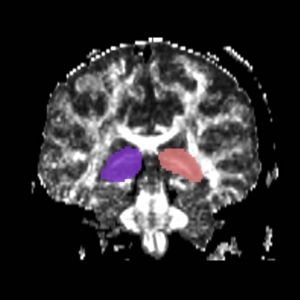

Fornix

The ROI1 was drawn on the sagittal slice, 5 slices superior to the anterior commisure (Fig. 8 & 10). The ROI2 was drawn on a coronal slice where the crux of the fornix was present. It was not always the same slice for both sides (Fig. 9 & 11).

Figure 8. Axial View of ROI 1

Figure 9. Coronal View of ROI 2 (left=11, right=13)

Figure 10. Sagittal View of Fornix, ROI 1 (both left and right)

Figure 11. Sagittal View of Fornix, ROI 2 (right)

The color coding of the resulting ROIs is as follows:

ROI 1: Left & Right (16)

ROI 2: Left(5) - Right(15)